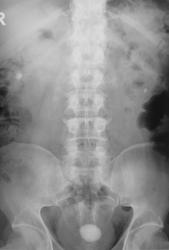

Пациент направлен на обзорную рентгенографию области почек и мочевыводящих путей.

Множественные конкременты МПС: слева в проекции нижней группы, справа скорее всего в средней группе и, конечно, в мочевом пузыре

Самое интересное то, что два дня тому пациенту было сделано УЗИ и было выставлено "объёмное образование мочевого пузыря" (опухоль), а перед этим, что и послужио поводом УЗИ, пациент хорошо "крованул".

Кровить могут и камни, точнее то, что они раздражают. При такой картине явлений всякого рода хронического воспаления-выше крыши, а при УЗИ скорее всего не отдифференцировали стенку пузыря и прилипший камень, но... Иногда на выделительных урограммах прекрасно видные краевые дефекты стенок за счет маленьких стелющихся опухолей, эти кровят будь здоров. Хотя, честно, на этом обзоре стенки четкие, ровные.

А с чем связано расширение левого мочеточника. Не думаю, что на УЗИ не заметитли камень. Он даёт такую эхотень, при его размерах, что спутать с образованием нельзя. Да и при смене положения должен перемещаться.

Фрагменты с увеличением.